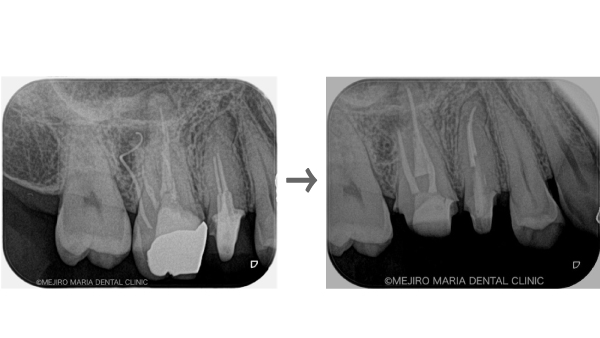

【症例】コンセプトを守った再根管治療(精密根管治療)